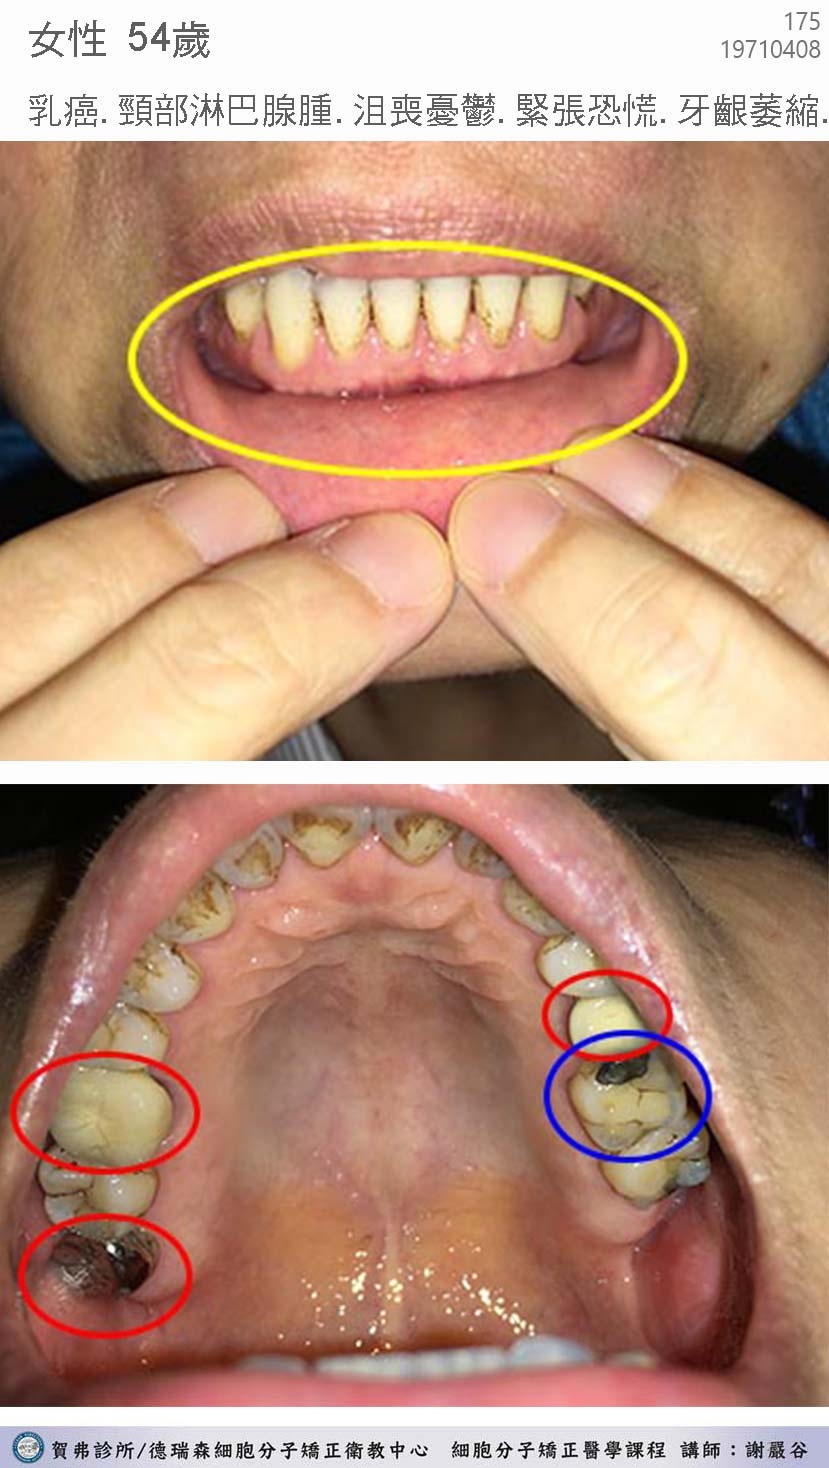

典型汞中毒症候群個案 hgscs0001